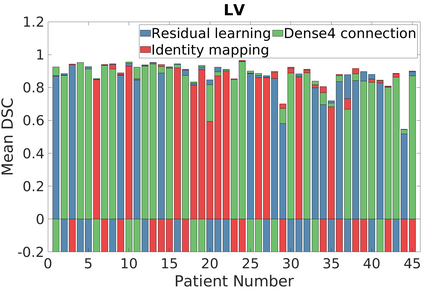

Deep Convolutional Neural Networks (DCNNs) are used extensively in biomedical image segmentation. However, current DCNNs usually use down sampling layers for increasing the receptive field and gaining abstract semantic information. These down sampling layers decrease the spatial dimension of feature maps, which can be detrimental to semantic image segmentation. Atrous convolution is an alternative for the down sampling layer. It increases the receptive field whilst maintains the spatial dimension of feature maps. In this paper, a method for effective atrous rate setting is proposed to achieve the largest and fully-covered receptive field with a minimum number of atrous convolutional layers. Furthermore, different atrous blocks, shortcut connections and normalization methods are explored to select the optimal network structure setting. These lead to a new and full-scale DCNN - Atrous Convolutional Neural Network (ACNN), which incorporates cascaded atrous II-blocks, residual learning and Fine Group Normalization (FGN). Application results of the proposed ACNN to Magnetic Resonance Imaging (MRI) and Computed Tomography (CT) image segmentation demonstrate that the proposed ACNN can achieve comparable segmentation Dice Similarity Coefficients (DSCs) to U-Net, optimized U-Net and hybrid network, but with significantly reduced trainable parameters due to the use of full-scale feature maps and therefore computationally is much more efficient for both the training and inference.